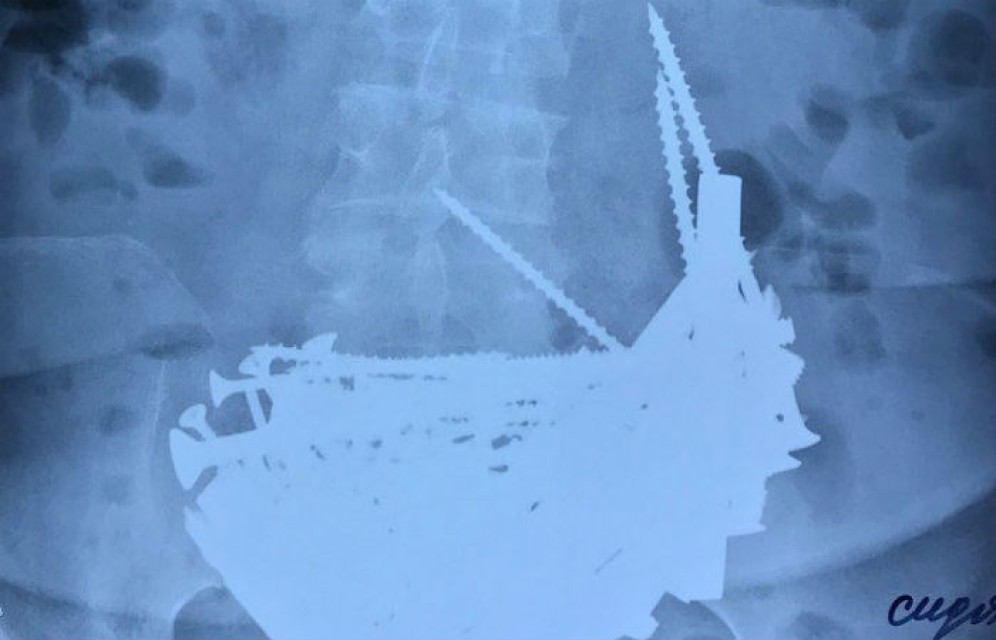

В Бурятии пенсионерка 14 лет лечила анемию гвоздями и шурупами

В Бурятии пациентка, которой врачи сообщили, что в ее организме не хватает железа, отправилась за витаминами в строительный магазин. С помощью гвоздей и шурупов она «лечилась» более 10 лет, передает НТВ.

Во время многочасовой операции в отделении хирургии медики достали из желудка пожилой женщины полторы сотни предметов — гвозди, шурупы, гайки, дверные шпингалеты и серебряную цепочку. Многое из того, что удалось извлечь, было ржавое и явно находилось в теле пациентки не один день. Как выяснилось, нездоровый аппетит пенсионерка проявляла на протяжении 14 лет. С тех самых пор, как ей поставили диагноз анемия — нехватка железа. Тогда слова врачей женщина восприняла буквально, и металлические изделия прочно вошли в ее рацион.

Врачи считают настоящим чудом то, что пенсионерке удалось выжить с таким грузом в желудке. Железные предметы она проглатывала каким-то немыслимым способом — так, что пищевод почти не пострадал. Однако в организме началось опасное воспаление, в больницу пациентка поступила с высокой температурой.